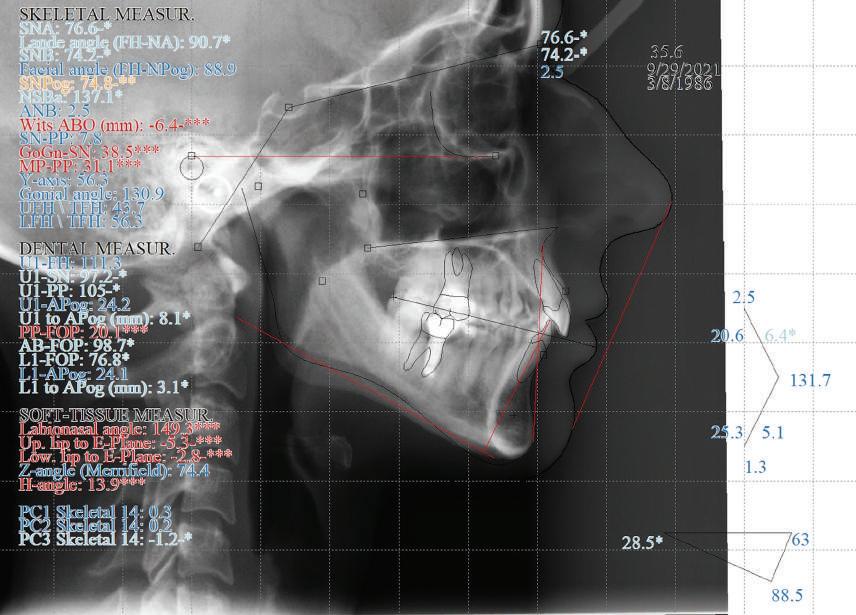

Dental Tribune Bulgarian Edition / октомври 2022 г. 17клиничен случай с алайнери леко струпване в долната че люст; несъответствие по Болтън (мандибуларен излишък от 3.06 мм във фронталната зона и общо 1.47 мм); издължено лице с лицева аси метрия; конвексен профил с ретруди рана долна челюст и проми нентен нос. На мястото на зъб #46 бе на лице имплант, а зъби #16 и 26 са ендодонтски лекувани. Тези зъби бяха асимптоматич ни, затова бе взето решение да се прави релечение само при нужда. Мъдреците липсваха. Анализът на телерентгеногра фията (фиг. 4) показа ретрог натна мандибула (SNB: 74.2°) и нормална инклинация на резците както в

(Ui–FH:

така и в

челюст

Цели на лечението и лечебен план Целите на лечението бяха следните: нивелиране и подреждане на зъбите и в двете зъбни дъги; отваряне на пространство за липсващия латерален резец; коригиране на отношенията при канините и моларите до клас I; и корекция на отклонението на срединната линия. Лечебният план включваше: корекция на отношенията при кучешките зъби и мола рите до клас I с дистализира не на максилата; отваряне на пространство в областта на #22 за поставя не на единичен имплант; корекция на срединната ли ния; и създаване на място за раз ширяване на зъб #12 и апрок симална редукция в долната челюст с цел подобряване на несъответствието по Болтън и осигуряване на подобра оклузия. Изпълнение на лечебния план Този случай бе изпълнен със системата за алайнери Invisalign (Align Technology). Одобреният първоначален лечебен план предвиждаше 49 алайне ра с дистализиране на задни те горни зъби до клас I (прибли зително с около 3.5 мм; фиг. 5). За бъдещия имплант в областта на липсващия латерал бе планирано пространство от 6.5 мм, докато във фронталния сегмент на долната челюст бе предвидена апроксимална редук ция. В дясната страна бутон за ластици клас II бе поставен на зъб #47 вместо на зъб #46, за да не се увреди короната на импланта. Понеже пациентката жи вееше в чужбина,

следните казуси: недобра оклу зия в дисталните зони по вре ме на дистализирането на гор ната челюст и накланяне на зъб #21 (фиг. 7). Последното се дължи на липсата на компози тен атачмънт на този зъб, каквото не бе зададено в пър Фиг. 4 Телерентгенография и цефалометричен анализ преди началото на лечението. Фиг. 5a–e Одобреният първоначален лечебен план. Фиг. 6a–h Снимки по време на лечението, показващи нуждата от внасяне на някои корекции. Фиг. 4 Фиг. 5a Фиг. 5d Фиг. 6a Фиг. 6d Фиг. 6f Фиг. 6b Фиг. 6e Фиг. 6g Фиг. 6h Фиг. 6c Фиг. 5e Фиг. 5b Фиг. 5c

Що се отнася до финалния це фалометричен анализ, лице вата височина

(LFH: 56.5 mm) и размерите на меките тъка ни останаха непроменени. На клонът на горните резци бе за пазен (Ui–FH: 115.8°), а долните резци бяха леко наклонени ве стибуларно (Li–APog: 30°; фиг. 16). ДИСКУСИЯ Липсата на зародиш на по стоянен горен латерален резец е налице при 3.5–6.5% от евро пеидната раса, като при жени е по-честа, отколкото при мъ жете в съотношение 3:2.8–10 Възможни са няколко лечебни подхода, включително замя ната му с преоформен канин, отваряне на място чрез орто донтско лечение и протетич но възстановяване, както и ав тотрансплантация. Устано вено е, че изборът за затваря не на място или за отваряне то му все още подлежи на дис кусия сред ортодонти и проте зисти.11,12 Според литературните дан ни затварянето на простран ството и замяната на липсва щия латерал с канин се предпо чита в случаи на едностранна липса на зародиш, балансиран профил, кучешки зъби и премола ри със сходна форма и цвят, дву челюстна протрузия или клас II малоклузия.13–15 Отваряне на пространство по-често се изби ра при клас I, наличие на диасте ми и треми в горната зъбна дъга или голяма разлика в размерите на канини и премолари.16 Скорошно проучване е уста новило, че изборът на лечение при конгенитално липсващ ла терал е пряко свързан със след ните фактори17: възрастта на пациента при започване на лечението; индивидуалните особености при всеки конкретен случай; и сътрудничеството между специалистите в лекуващия екип. Макар да има проучвания, фа воритизиращи леченията със затваряне на място11,18, всеки случай трябва да бъде оценяван индивидуално. В презентирания в тази статия случай бе взето решение за отваряне на мяс то и протетично възстановя ване, понеже целта бе да се по стигнат клас I отношения при канините и моларите, както и по-широка усмивка. За да се из бегнат компромиси, след лече нието бе постигнат клас I при моларите и кучешките зъби, несъответствието по Болтън бе подобрено и срединната ли ния бе коригирана. Други изслед вания демонстрират отлични естетични и функционални ре зултати при лечение с отваря не на място и протетична ре хабилитация.19 И двете лечеб ни модалности са подходящи за третиране на вродена лип са на зародиш на латерал и да ват сходни функционални и па родонтални резултати20, като при едно проучване

ти и клас II ластици е устано вено, че осигурява достатъч на дистализация без промяна на лицевата височина.23 Както се видя от цефалометричния анализ, точно това бе постиг нато и в представения случай като се има предвид, че лице вата височина остана същата като първоначалната. Предвид леката тенденция към дистал Фиг. 8a–e Поръчаните допълнителни алайнери. Фиг. 9 Панорамна рентгенография след края на лечението. Фиг. 10a–c Странични (а и с) и фронтална интраорални снимки след края на ортодонтското лечение и поставянето на импланта (b). Зъб #12 все още не беше протезиран. Фиг. 11а и b Оклузални снимки след ортодонтското лечение. Фиг. 7a Фиг. 8a Фиг. 7d Фиг. 8d Фиг. 9 Фиг. 10a Фиг. 10b Фиг. 10c Фиг. 11bФиг. 11a Фиг. 7b Фиг. 8b Фиг. 7e Фиг. 8e Фиг. 7c Фиг. 8c Фиг. 7a–e Интраоралната ситуация по време на лечението. клиничен случай с алайнери